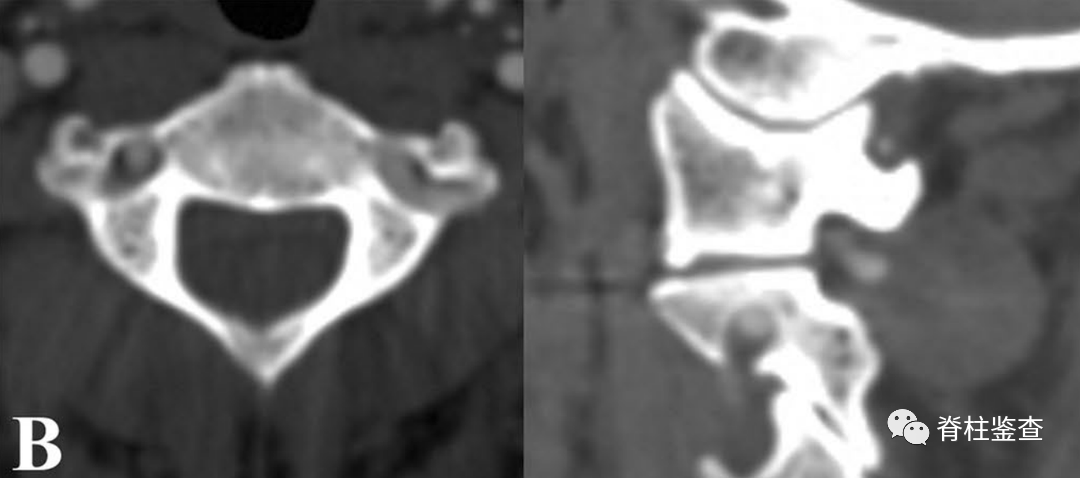

B:椎弓根狭窄,椎动脉高跨右侧椎弓根螺钉置入风险高

B:椎弓根狭窄,右侧椎动脉高跨

椎弓根狭窄和椎动脉高跨的情况下,C2内侧开窗技术可实现安全的C2椎弓根螺钉置入,通过破坏椎管内壁并占用部分椎管空间以避开椎动脉,并不会损伤脊髓;同时,可以提供三柱固定。因此,当椎弓根狭窄或椎动脉高跨时,C2内侧开窗技术可作为一种代替方法。